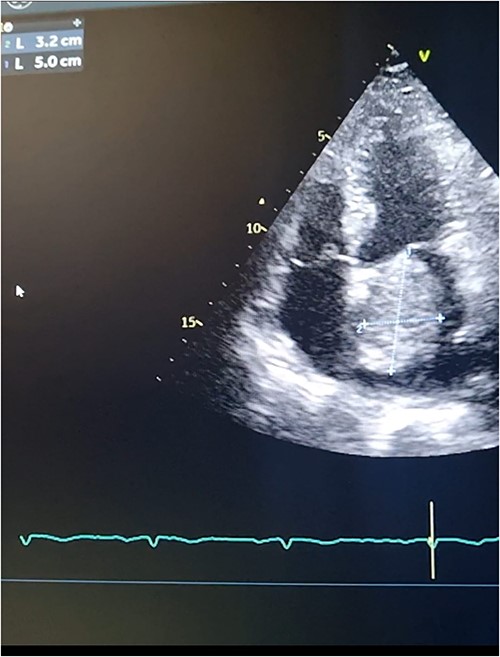

Meanwhile, transthoracic echocardiography was done to investigate the cause of loud S1 and fingers clubbing. The Echocardiography showed a large heterogeneous mass attached to the fossa ovalis in the left atrium. (Figs 1A, B and 2). This was followed by obtaining a computed tomography (CT) scan of the chest to investigate for other causes of hemoptysis. The CT scan showed no other identifiable etiology precipitating hemoptysis. Thus, it was determined that elevated pressure in the pulmonary vessels secondary to obstruction in the mitral valve blood flow caused hemoptysis in the presented case. A preoperative diagnostic coronary angiography showed normal coronaries with no evidence of stenosis.

Transthoracic echocardiography. 2D measurements of the LA mass measuring 5 cm * 3.2 cm.